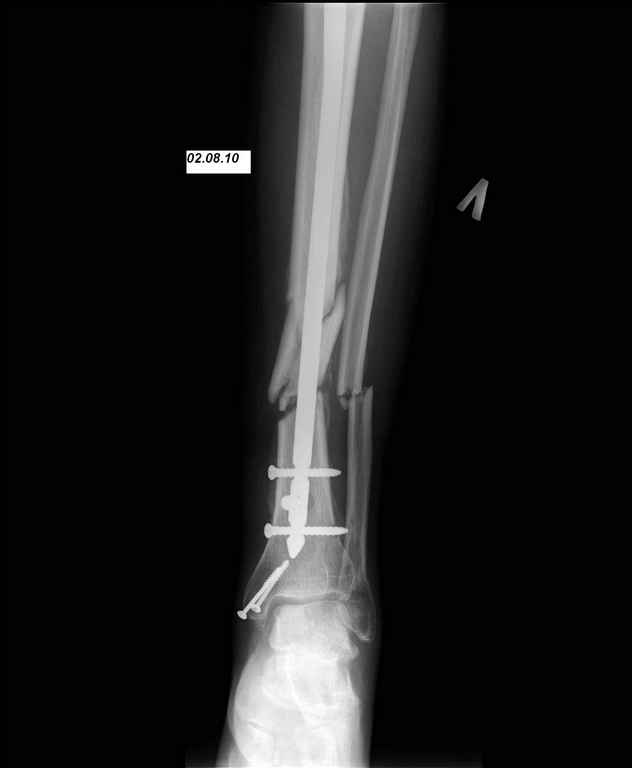

24.03.10 выполнены операции - БИОС перелома большеберцовой кости левой голени (штифт Synthes), остеосинтез перелома внутренней лодыжки левой голени винтами. Послеоперационный период протекал без осложнений. Выписан на 10 сутки. Амбулаторно не наблюдался.

И вот опять объявился. Снимки и фотографии в приложении(первичные потеряны). Около 1 месяца назад появились боли в области нижней трети голени в проекции дистальных блокирующих винтов, передвигался с нагрузкой 50% (сам для себя так решил, сам себе разрешил). Путешествовал по Волгоградской области, обратился к травматологу, со слов перевязывали, лечили антибиотиками. Лучше не стало. Вернулся домой.

Вчера госпитализирован в отделение. Локально умеренный отек, кожная температуа не повышена. По передней поверхности в области дистального блокируюшего винта свищ, скудное гнойное отделяемое, винт удален на перевязке зажимом. «Старый» свищ не функционирует. Взят бак. посев, ждем результат.